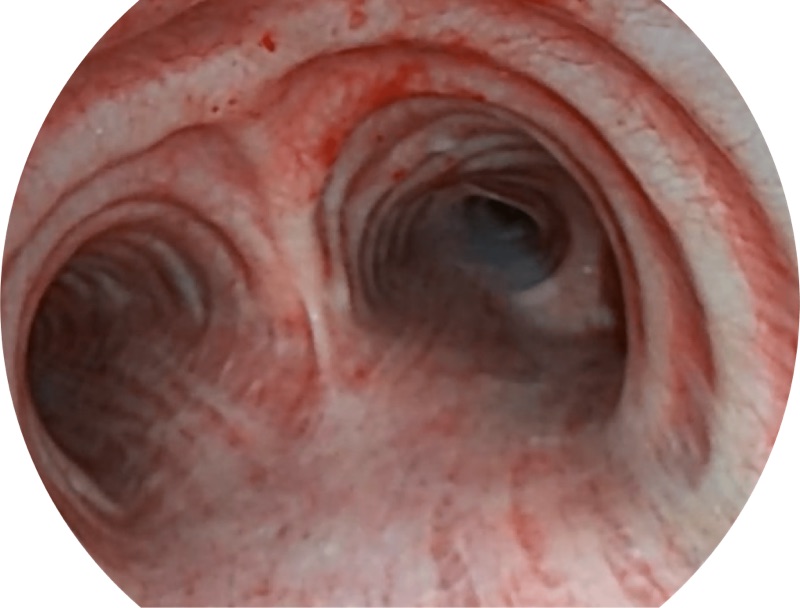

EB-5H20具有4.9mm外径及2.0mm钳道提升对外围支气管检查能力

白光